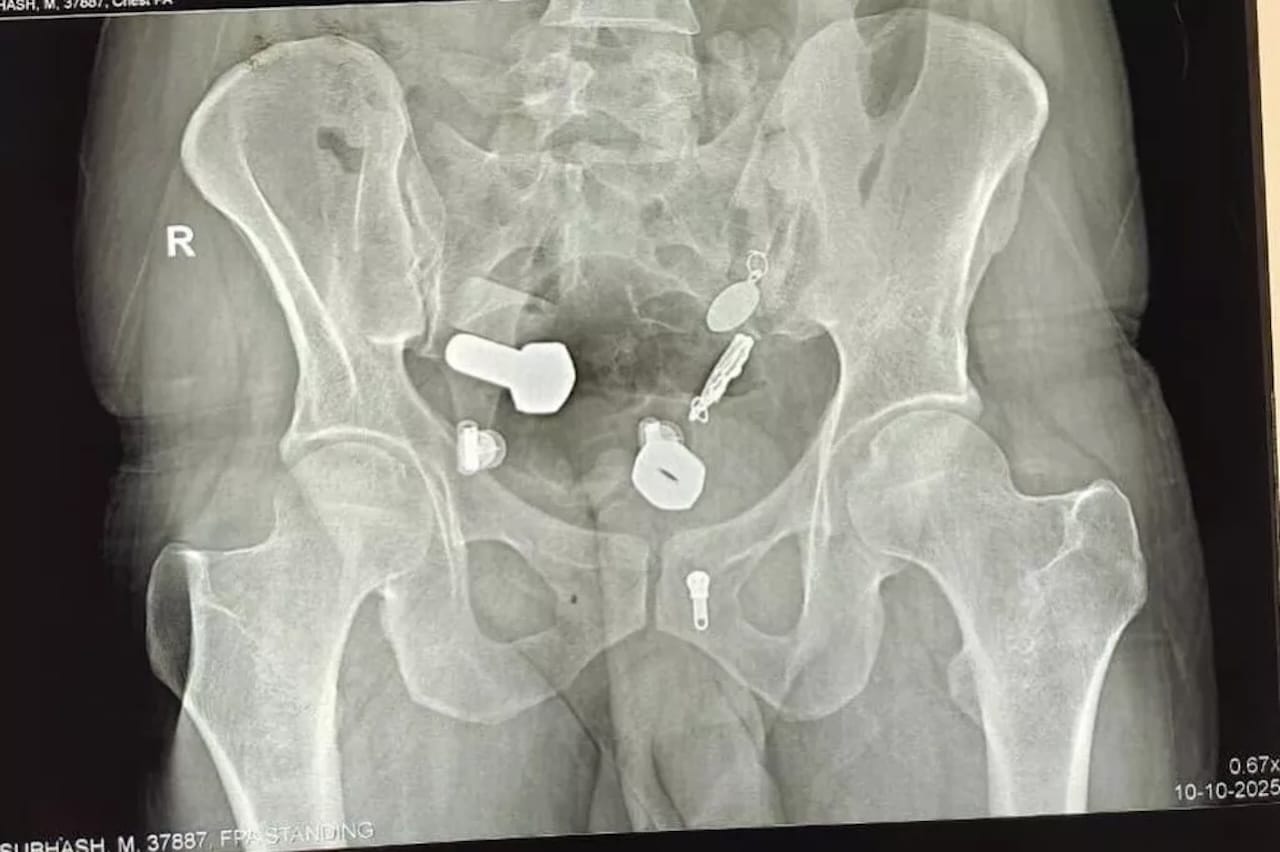

C’est lors d’un scanner de routine que les médecins ont fait une découverte qui les a laissés sans voix : une montre entière était coincée dans l’œsophage du patient. Plus surprenant encore, son intestin contenait un véritable assortiment d’objets métalliques, notamment des écrous et des boulons. Une collection qui ne manque pas d’interpeller sur les circonstances ayant mené à cette situation!

L’équipe médicale a donc dû procéder à une intervention chirurgicale plus conséquente. Durant une opération de trois heures, ils ont pratiqué une petite incision abdominale qui leur a permis d’extraire l’ensemble des corps étrangers. Les images partagées par l’équipe chirurgicale montrent l’impressionnante collection d’objets métalliques récupérés dans le corps du patient.